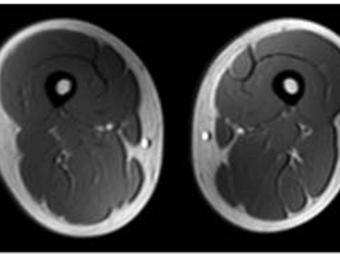

Low-Intensity Exercise during Adolescence May Prevent Schizophrenia